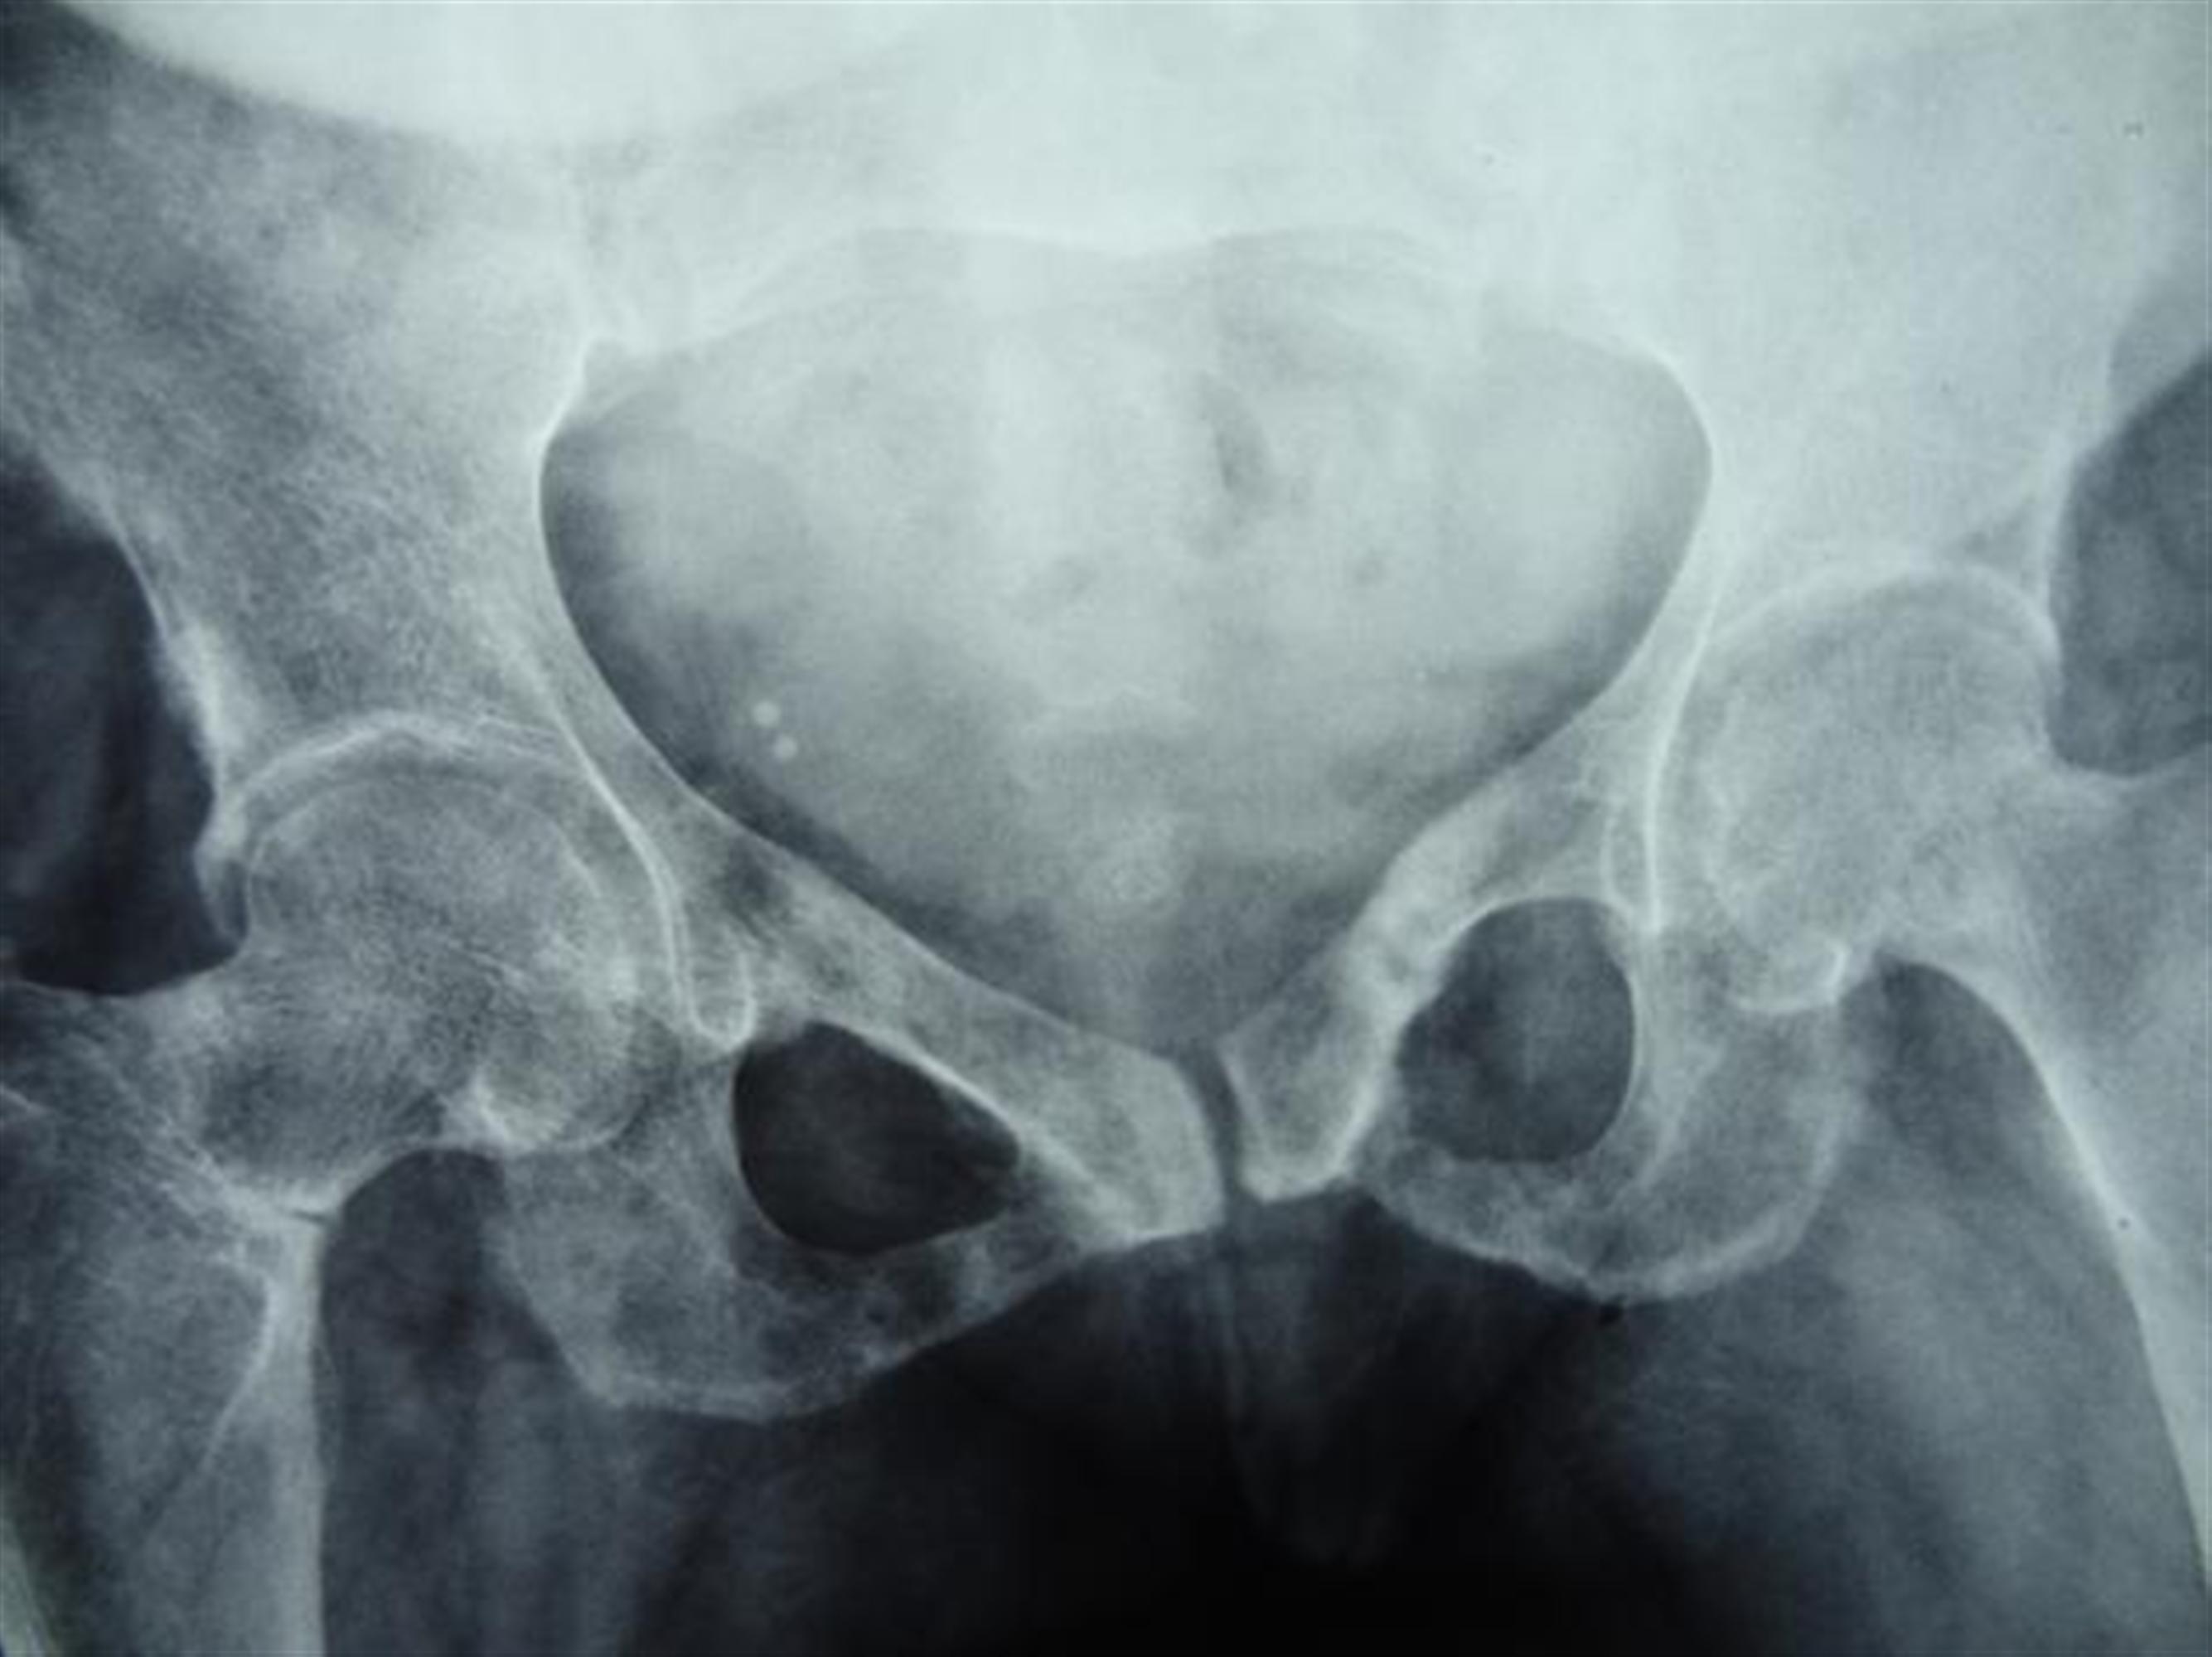

Osteomalacic Pelvis Looser Zones Radiology Looser zones, also known as cortical infractions, milkman lines or pseudofractures, are wide, transverse lucencies with sclerotic borders. Pseudofractures or looser's zones are a hallmark of osteomalacia, seen as lucent lines in the femoral neck. Looser zones, also known as cortical infractions, milkman lines or pseudofractures, are wide, transverse lucencies with sclerotic borders. The term looser’s zones, is eponymous of. Looser Zones Radiology.

From radiopaedia.org